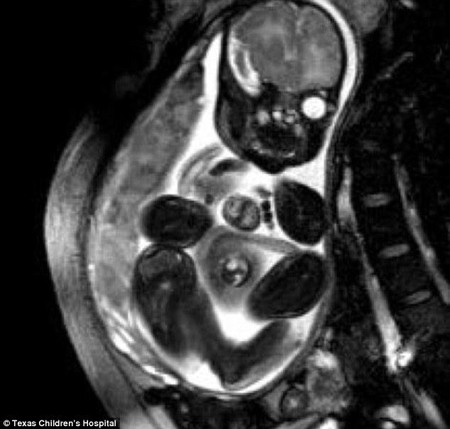

据英国《每日邮报》1月24日报道,美国德克萨斯州一名出生时先天心脏便长在体外的女婴,在接受手术后,已于当地时间23日出院回家。据悉,经过手术,这颗小心脏已安全地回到她的胸腔内。